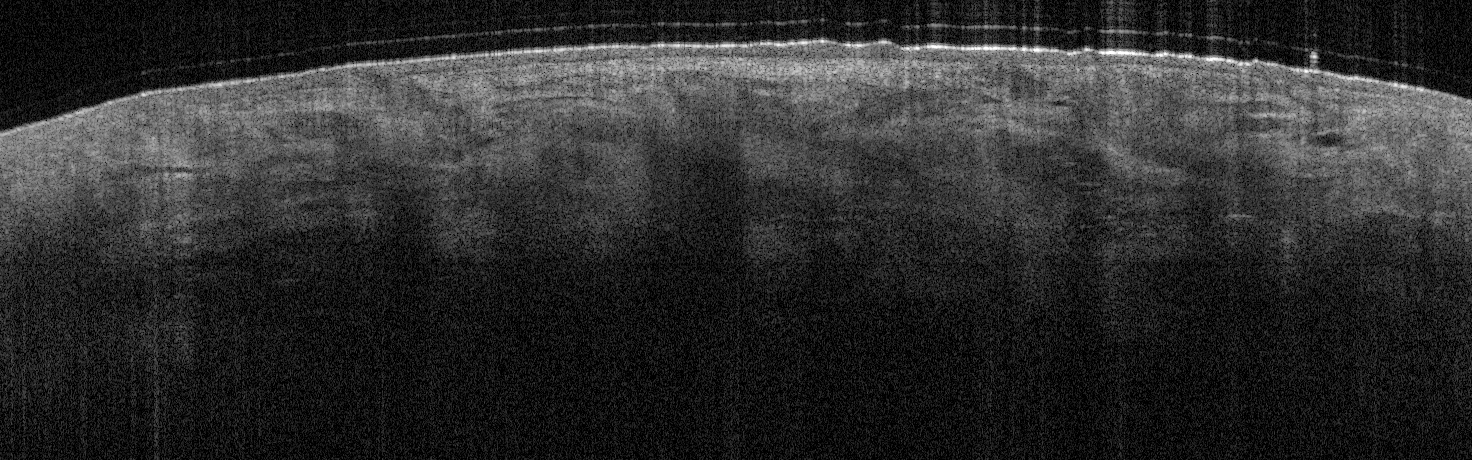

VA1: Right Forearm, Normal